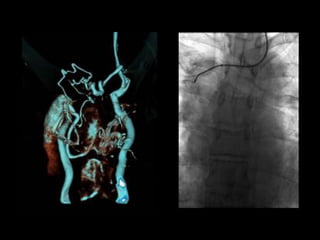

65M with metastatic lung ca and recent PEs. An IVC filter was placed but did

not fully deploy. A second IVC filter was placed above the first one.

120cc contrast, diagnostic delay = 70sec